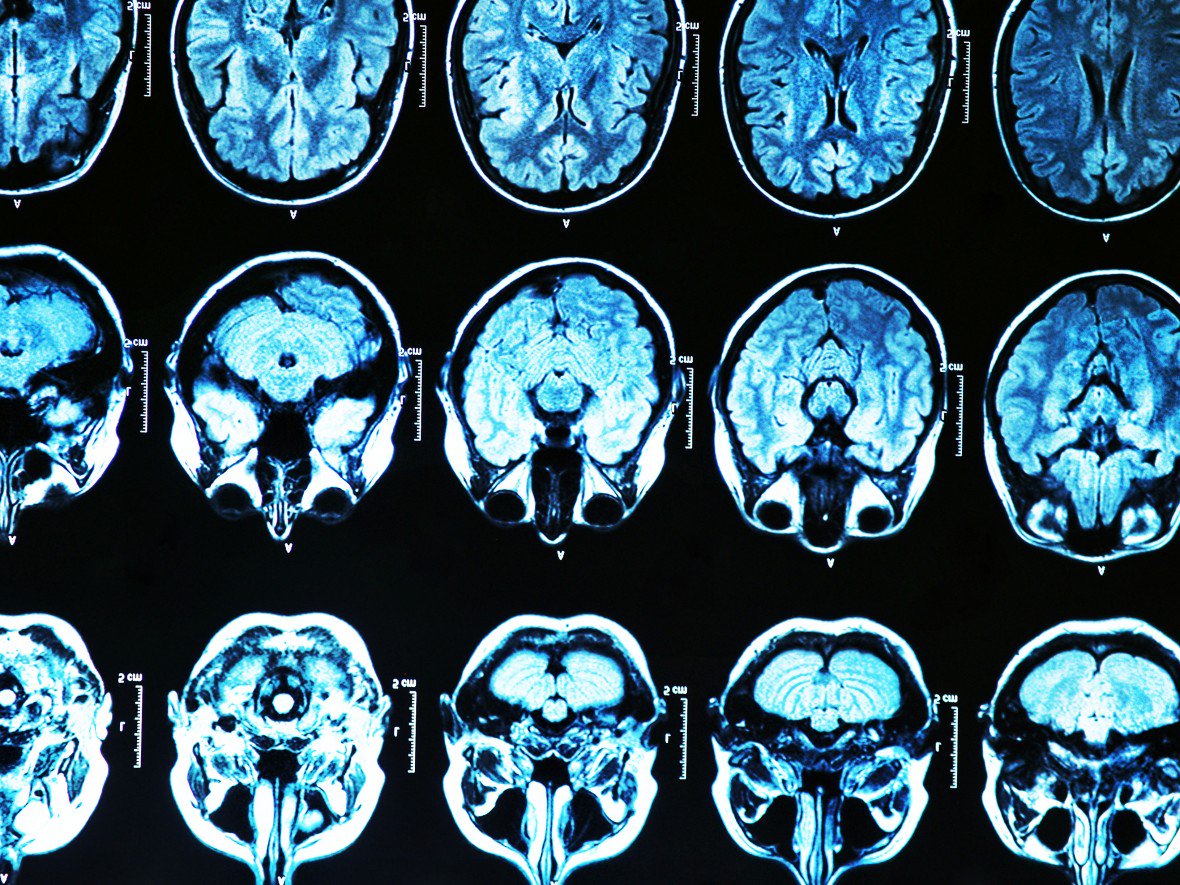

روش ژنتراپی جدید برای مقابله با آلزایمر

شاید امروز نتوانیم ژنها را تغییر دهیم، ولی پزشکان نیویورک سیتی میگویند از ابتدای ماه مه شروع به تست یک روش ژن تراپی جدید خواهند کرد. در این روش به مغز افرادی که بدترین نوع ژنهای APOE را دارند، دوز بسیار بالا از نسخه کم خطر تزریق میشود.

این دوره آزمایشی بحرانی که در Weill Cornell Medicine در منهتن انجام میشود، یک تاکتیک جدید در برابر بیماری فراموشی و همچنین راهی تازه در ژن تراپی است.